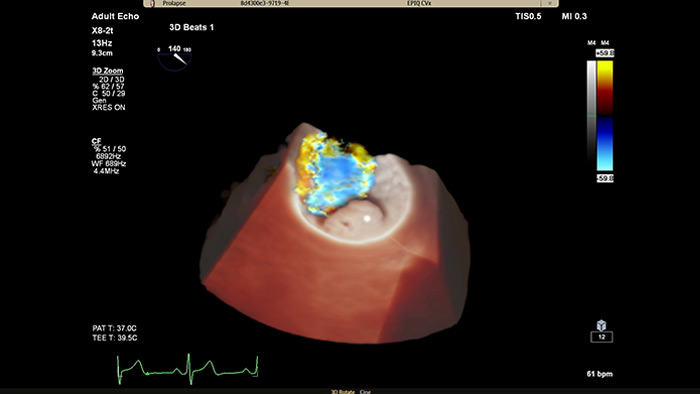

TrueVue Color

Für eine verbesserte Darstellung der Herzanatomie in der transthorakalen und transösophagealen Echokardiographie erleichtert Philips TrueVue Color mit seiner virtuellen Lichtquelle die Visualisierung von Defekten und die Erkennung der Tiefe innerhalb der Strukturen.